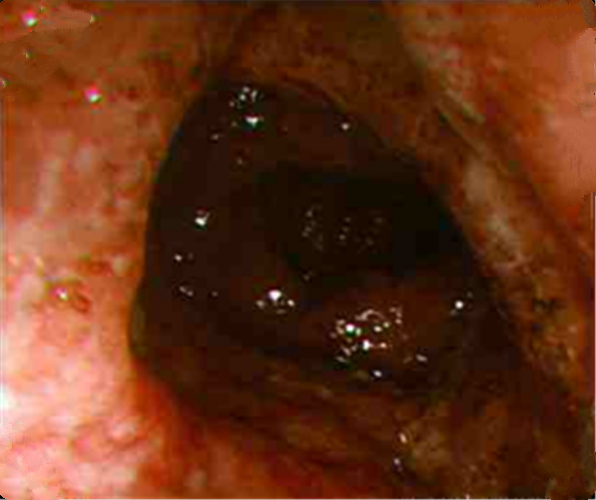

嚴重慢性結腸炎的

嚴重慢性結腸炎腐爛的

缺血慢性結腸炎患者

缺血性慢性結腸炎的